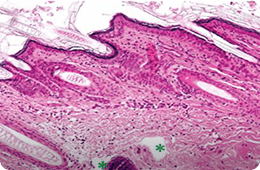

1064 PS

침투깊이 : 499.98~935.23 μm

침투깊이 : 257.12~287.38 μm

출처 : Effect of fractional picosecond laser therapy using a diffractive optical lens on histological tissue reaction, Journal of cosmetic and laser therapy, 2024